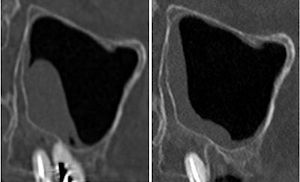

77-jährige Patientin (30.06.2025 / 404)

14 Tage nach der Extraktion war das Schleimhautpolster nur noch halb so gross:

09.07.2025 23.07.2025